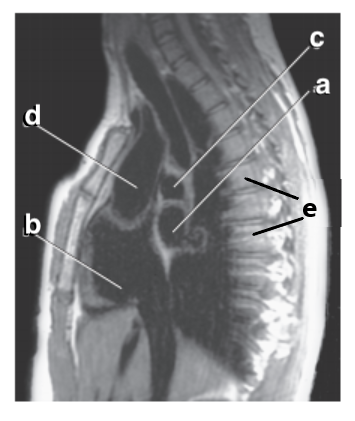

What is letter f ?

Diaphragm

What is letter e ?

Aortic Arch

Which letter is the descending thoracic aorta ?

e

What is letter g ?

Descending thoracic aorta

What is letter d ?

Thoracic vertebra